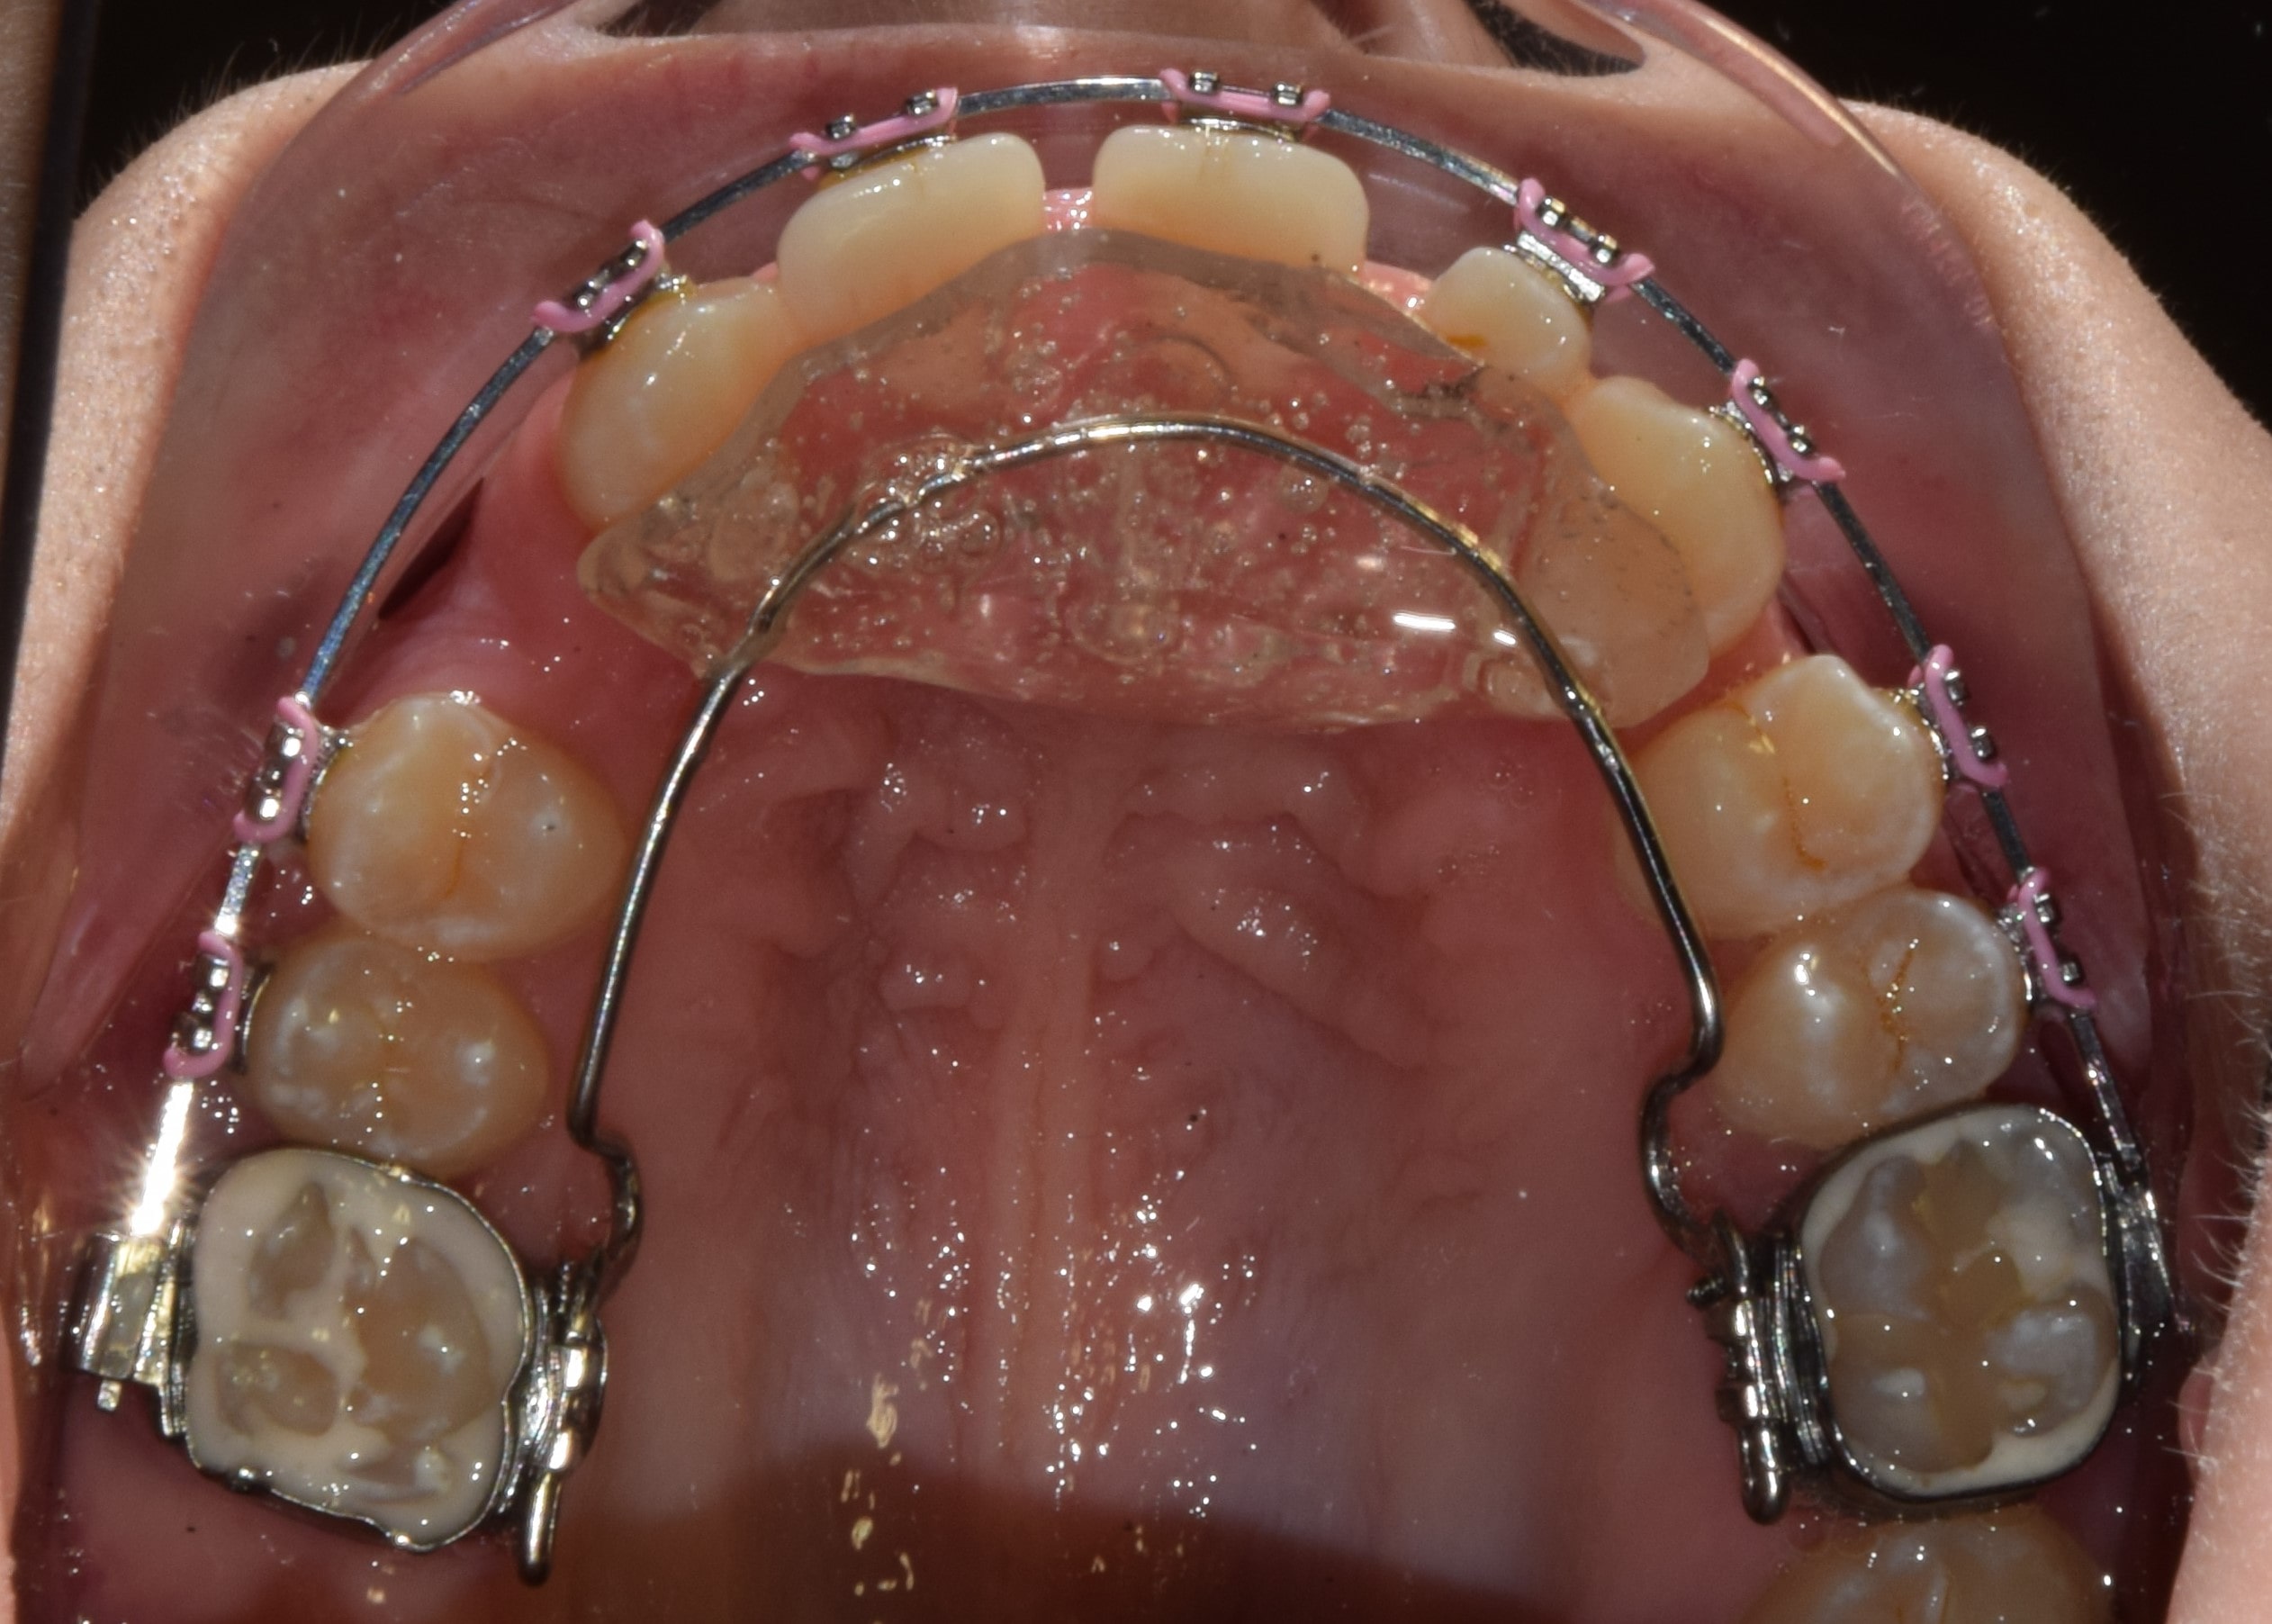

A felső első őrlőfogakon gyűrűvel rögzülő, a szájpadot vékony acélívvel áthidaló rögzített fogszabályzó készülék, mely közepén (a szájpadon) apró golyó található. Ezt a golyót nyelvvel pörgetni lehet, ezért gyerekeknél gyakran használjuk használjuk nyelvlökéses nyelés korrekciójára. A készülékkel játékosan érhető el a nyelv helyes pozícióba szoktatása.

A kép forrása: https://kieferorthopaedie.com/